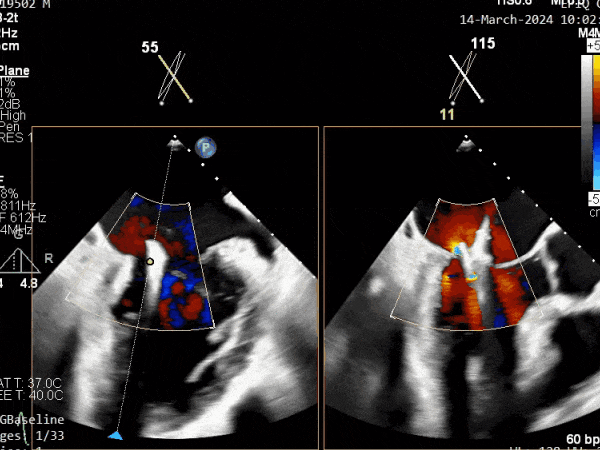

瓣膜夹释放前评估,二尖瓣反流减轻

瓣膜夹释放前评估,二尖瓣平均跨瓣压差及瓣口面积

释放瓣膜夹后评估,二尖瓣呈双孔,外侧仍有残余反流

第二个瓣膜夹释放前评估,二尖瓣反流减轻

第二个瓣膜夹释放前评估,二尖瓣平均跨瓣压差及瓣口面积

第二个瓣膜夹释放后评估,二尖瓣呈双孔,外侧仍有残余反流

第三个瓣膜夹释放后评估,释放后评估,二尖瓣呈双孔,组织桥张力合适,瓣膜夹轴向与二尖瓣闭合线垂直,无残余反流

肺静脉血流频谱恢复为收缩期正向